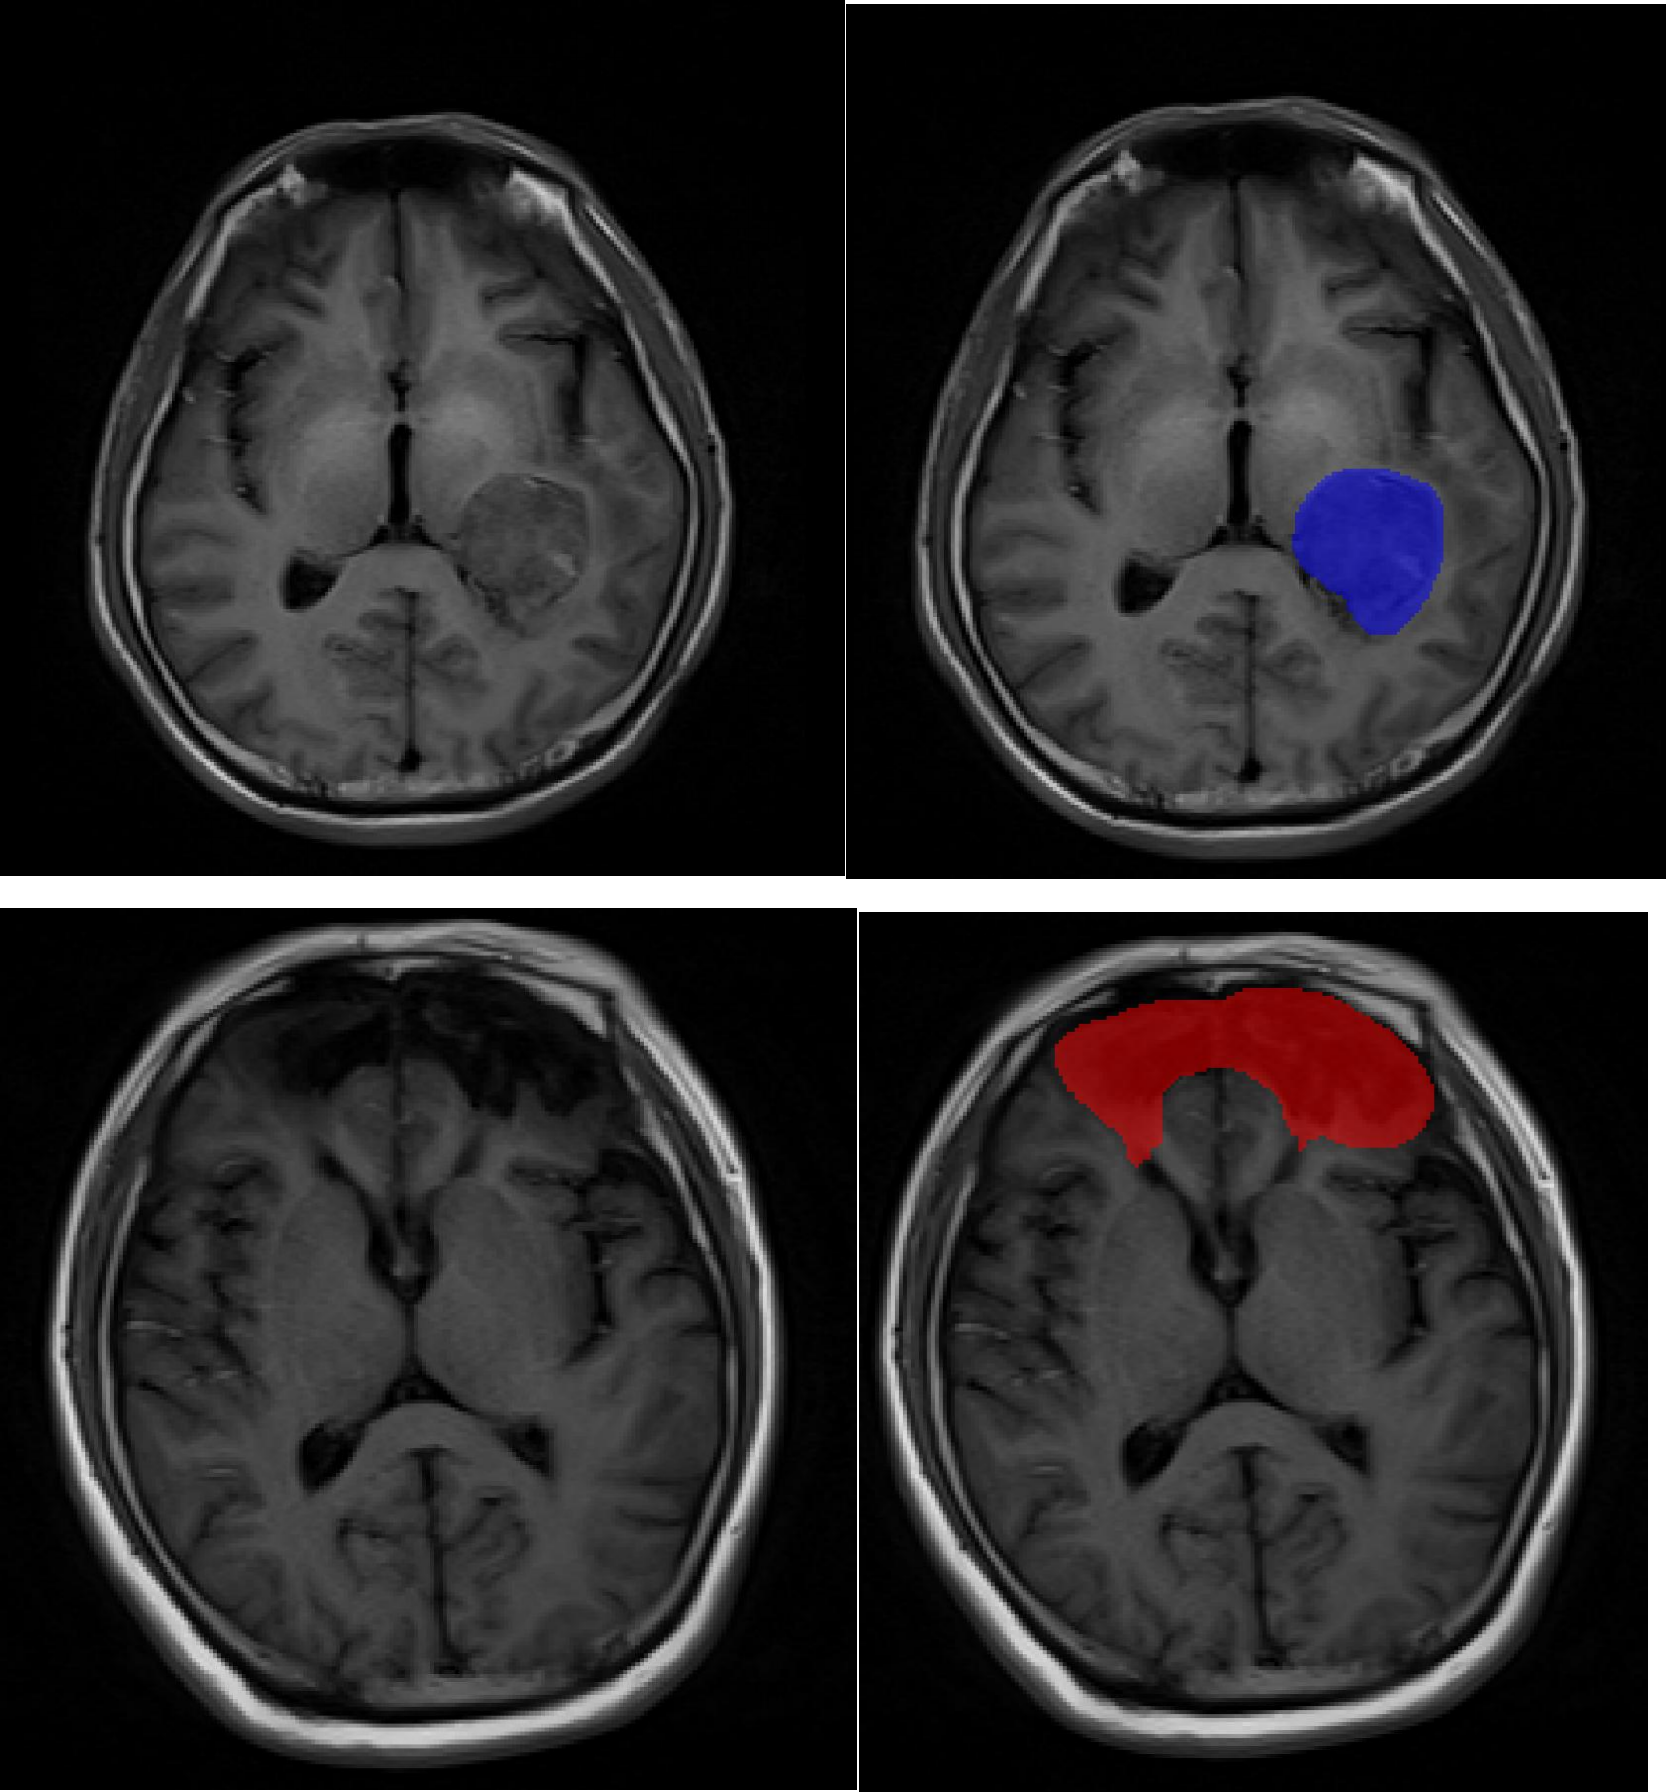

智慧医疗解决方案

面向医疗影像、辅助诊断、健康管理等领域,提供临床级的高质量医疗数据服务。

智慧医疗

面向医疗影像、辅助诊断、健康管理等领域,提供高质量医疗数据服务

• 医学影像数据